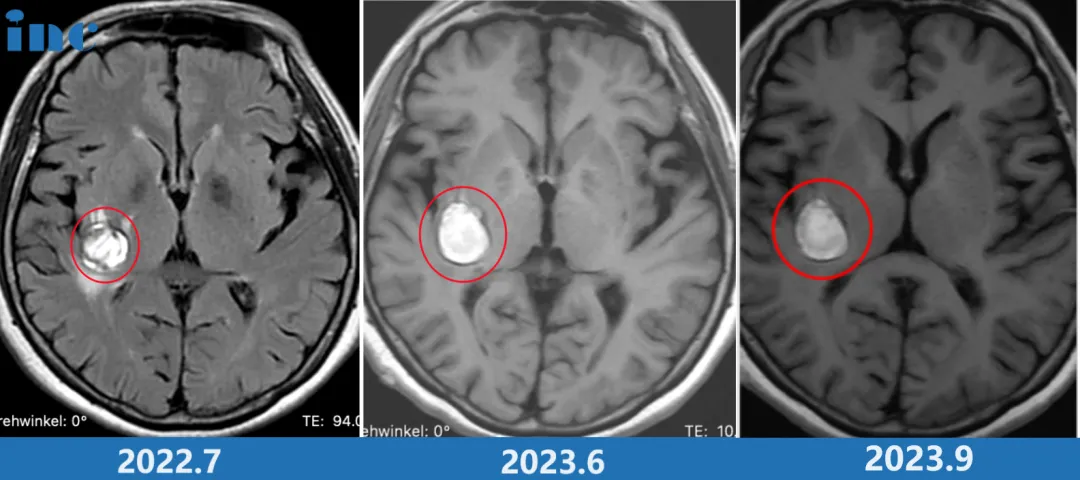

可症状没见好转,反而悄悄加重。2022年,柯阿姨去医院复查时做了头部核磁共振(MRI),结果让所有人都慌了:右侧基底节区海绵状血管瘤,病灶大小约18×19mm。

医生建议“定期复查MRI,密切观察病灶变化”,然而含血病灶逐年增大,从2022年的18*19mm到2023年的24*19mm,但是多名专家表示不赞成手术治疗,更是明确表示术后偏瘫失语可能性大。

柯阿姨紧急做了新的MRI,结果显示:病灶又增大了!当巴教授查看最新核磁图像后,告知患者随时会有出血风险,需要立即手术。